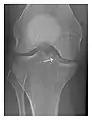

a

b

c

Figure 3: A 26-year-old man presenting with wrist pain after being assaulted. (a) Initial anteroposterior radiograph shows a subtle linear lucency within the scaphoid extending to the scaphocapitate articular surface that was overlooked (arrow). (b) Initial "scaphoid" view was negative. (c) Followup anteroposterior radiographs, 12 days later, shows obvious scaphoid fracture (arrows).[1]